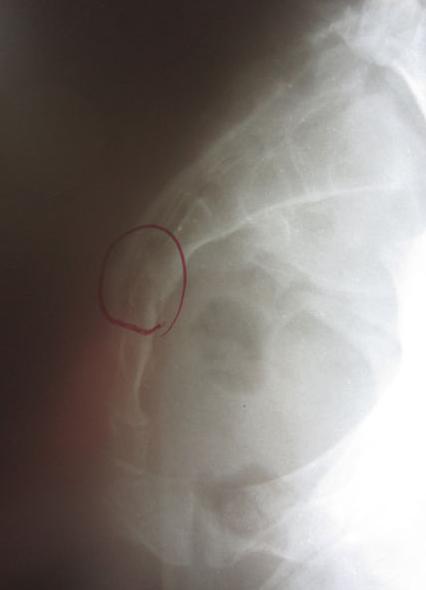

Mr H在摔车之后尾椎部位十分的疼痛,疼痛遍及腰部与骨盆周边,早晨更是痛到无法起身起床。经过检查后虽然没有骨折但是发现有尾骨挫伤的情况。经过徒手调理之后,疼痛立即获得舒缓。

Miss C不慎由楼梯摔落直接跌坐在屁股上,在尾椎骨持续疼痛数天之后由医师评价发现有尾骨骨折裂伤的情况。当下给予止痛药与肌肉松弛剂作为治疗。但疼痛状况却未见明显改善。经评价发现骨盆有严重歪斜的状况,在调整骨盆歪斜的问题之后疼痛状况大幅改善,可完全不需止痛药。三个月后回诊医师判定尾椎骨折部位愈合良好。